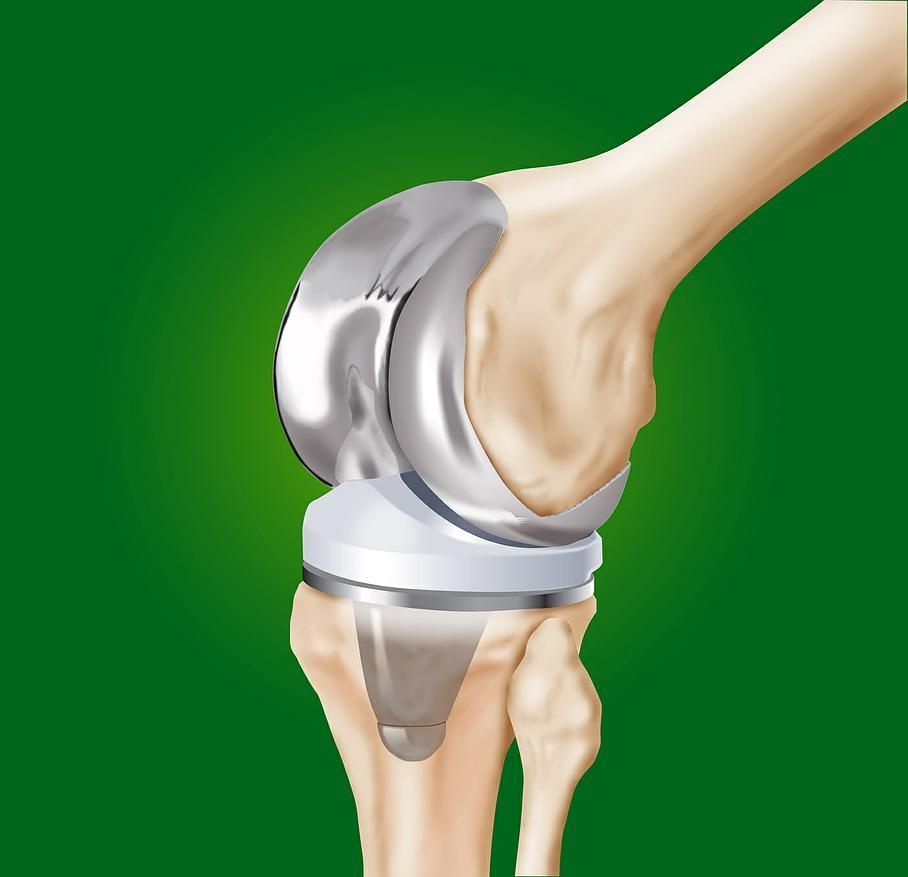

L’arthrose du genou ou gonarthrose:

L’évolution d’une arthrose du genou se fait par usure du cartilage et apparition de douleurs qui deviennent handicapantes pour la personne. Une fois le cartilage abîmé, il n’existe pas de solution médicale pour le reconstituer. Dès lors, un remplacement de l’articulation par une articulation artificielle, nommée prothèse, s’avère nécessaire.

Ceci se fait par une intervention chirurgicale, en préservant les muscles et les tendons. L’opération se fait quand les douleurs surviennent à la marche, et des fois la nuit, et qu’elles ne sont plus soulagées par aucun traitement médical. Il peut donc s’écouler plusieurs années entre la découverte de l’arthrose de la hanche et la mise place d’une prothèse.

L’intervention permet de rétablir une marche indolore et de reprendre certaines activités sportives. Le taux de satisfaction des patient(e)s est très élevé.